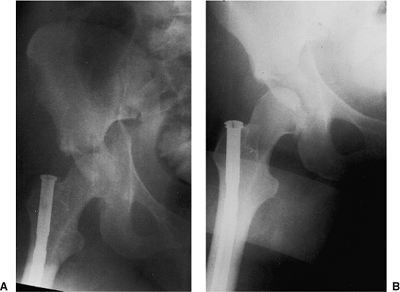

![]() |

Figure 41.5. A–C.

AP and 45-degree oblique hip x-rays after emergent reduction of the hip dislocation. The juxtatectal transverse-acetabular fracture with an associated posterior wall fracture is more completely delineated. |